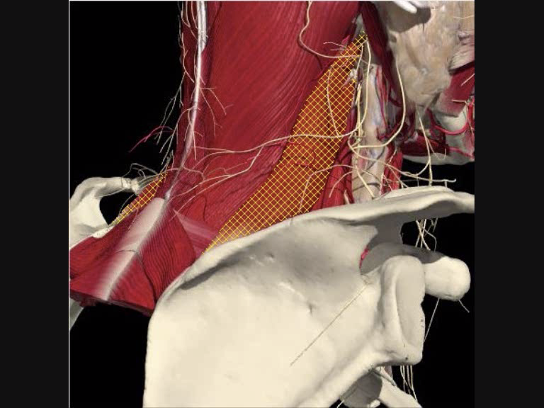

The Interscalene Groove

- The interscalene groove lies immediately behind the lateral border of the clavicular head of the sternocleidomastoid muscle at the level of the cricoid cartilage (C6)

- Approximately 1cm above the separation of the sternal and clavicular heads of the sternocleidomastoid muscle.

Structures to Avoid

Brachial Plexus

The BP lies inferior to a line from the posterior margin of the sternomastoid at the level of the cricoid cartilage to the midpoint of the clavicle

The BP lies inferior to a line from the posterior margin of the sternomastoid at the level of the cricoid cartilage to the midpoint of the clavicle. Scalenus medius is behind and above line.

Interscalene Groove & Brachial Plexus

Interscalene groove